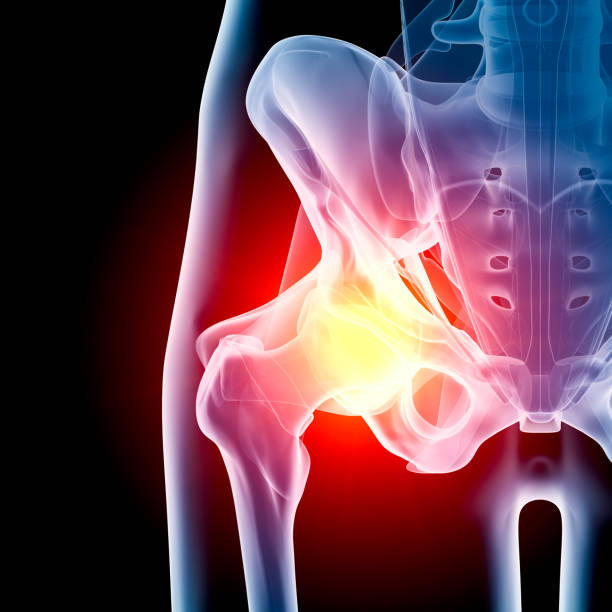

고관절은 걷기, 앉기, 서기 등 일상생활의 모든 움직임에 중요한 역할을 하는 부위입니다. 하지만 이 부위에 통증이 생기면 움직임이 크게 제한되고 삶의 질이 떨어질 수 있죠. 오늘은 많은 분들이 궁금해하는 고관절 통증 증상 10가지와 치료 정리에 대해 자세히 알아

보겠습니다.

고관절 통증은 단순한 근육통에서부터 관절염, 골절, 신경계 문제까지 다양한 원인으로 발생할 수 있습니다. 증상과 원인을 정확히 파악하는 것이 빠른 치료와 예방의 첫걸음입니다. 특히 고관절 통증 증상 10가지와 치료 정리를 통해 본인 상태를 체크해보는 것이 중요합니다.